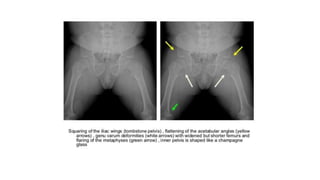

(6) The pelvic cavity

• is short and broad, also called as champagne-glass appearance.

• There’s squaring of iliac wings with some roundening of corners on a

frontal projection (elephant ear shaped iliac wings).

• The inferior margins of iliac wings and the roofs of acetabulum are flat

and horizontal.

• The sacrosciatic notches are small with an exaggerated sacral tilt and

large, anteriorly protruding sacral promontory.

Radiograph of pelvis (D) shows short and broad pelvis (*), horizontal acetabuli (arrow) and round iliac